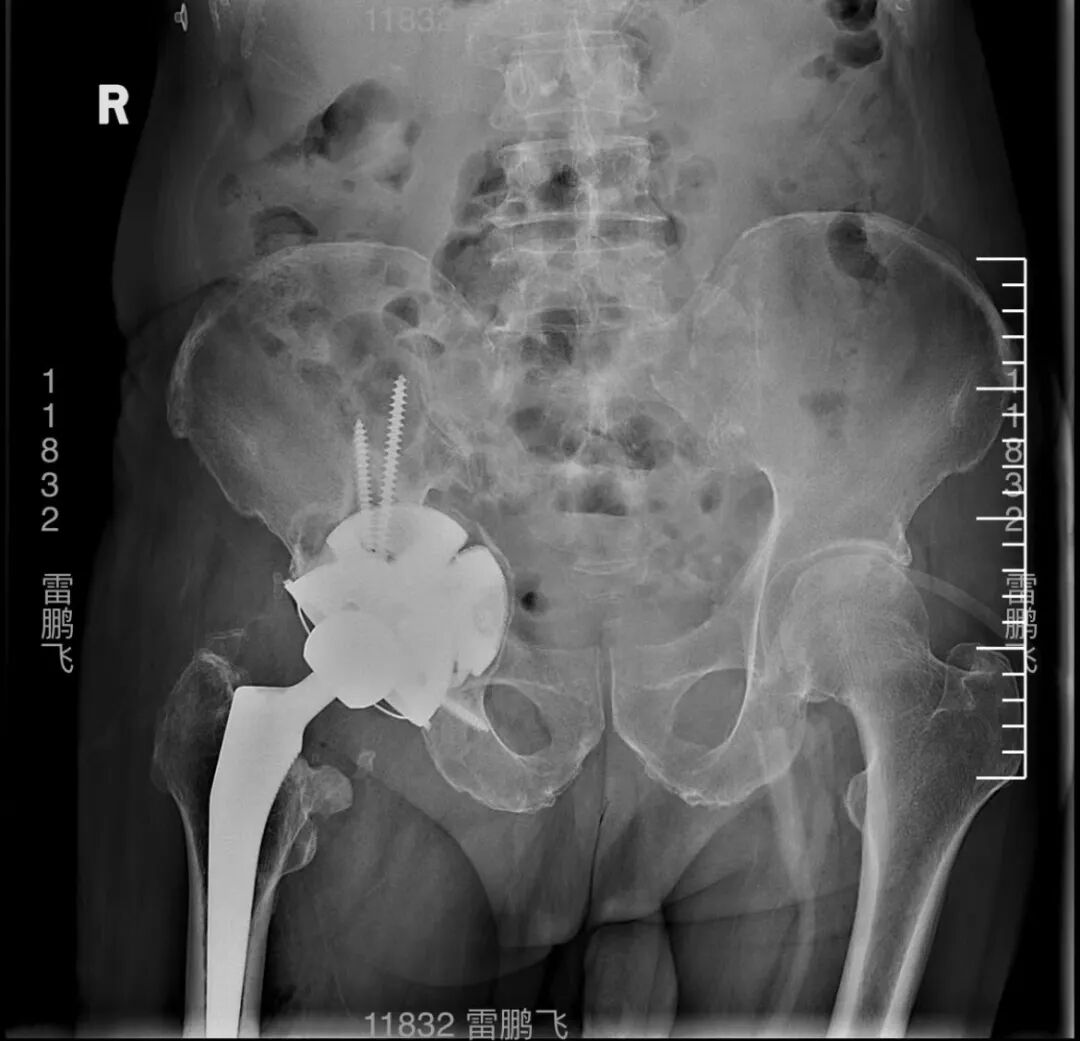

近日,由浙江大学医学院附属第一医院雷鹏飞教授团队顺利完成浙江首台VTS可视化智能辅助系统配合爱康HDR翻修系统+个性化定制3D打印多孔金属补块的复杂翻修手术。术中使用72毫米直径髋臼杯,结合3D打印个性化定制翻修补块,在VTS系统辅助下精准放置于规划位置,成功修复髋臼巨大骨缺损。

术后雷鹏飞教授表示,VTS系统与HDR系统首次搭档获得了良好的术后效果,VTS系统的引入让复杂手术简单化,术前规划让手术更安全,术中辅助指引让手术更精准。HDR定制外杯采用非组配设计,假体整体为EBM技术3D打印多孔结构,具有较高的粗糙度和摩擦系数。由于无需设计与内衬的连接结构,因此螺钉孔的布置更加灵活,为俗称的“满天星”设计,便于在残留的宿主骨上进行螺钉固定,实现牢靠的初始稳定性。